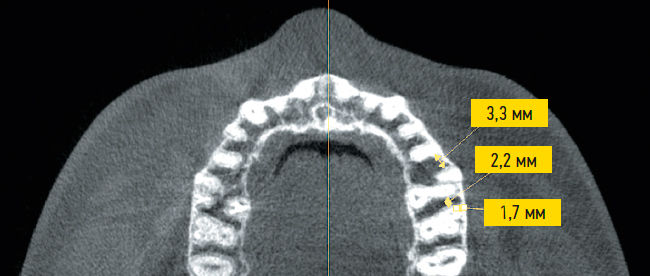

Рис. 1. Аксиальный срез томограммы: расчет межкорневого расстояния.

Fig. 1. Axial section of the tomogram: calculation of the interradicular distance.

- расстояние между корнями зубов в пришеечной области корня зуба (область Б) (см. рис. 1);

Медианные значения межкорневого расстояния в области верхушек корней зубов (у верхнечелюстной пазухи), составили для области А 2,90±1,4 (2,3–3,3) мм; для области Б 2,35±0,65 (1,75–3,13) мм (рис. 3). Среднее расстояние от корня зуба до компактной пластинки альвеолярного отростка верхней челюсти в области Б составило 2,36±0,98 мм. В современной ортодонтической практике используют микроимплантаты диаметром до 2 мм, имеющие коническую, сходящуюся форму кончика [11]. Следует отметить, что у 30% пациентов в области Б и у 15% пациентов в области А линейные размеры межкорневого пространства составляют менее 2 мм, в связи с чем потребуется сделать выбор либо имплантатов меньшего диаметра, либо альтернативной области для имплантации.